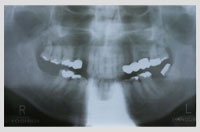

症例1 一般的な症例 年齢61歳 男性

初診時の状況

・左下奥歯が歯周病で咬めないとの事で来院